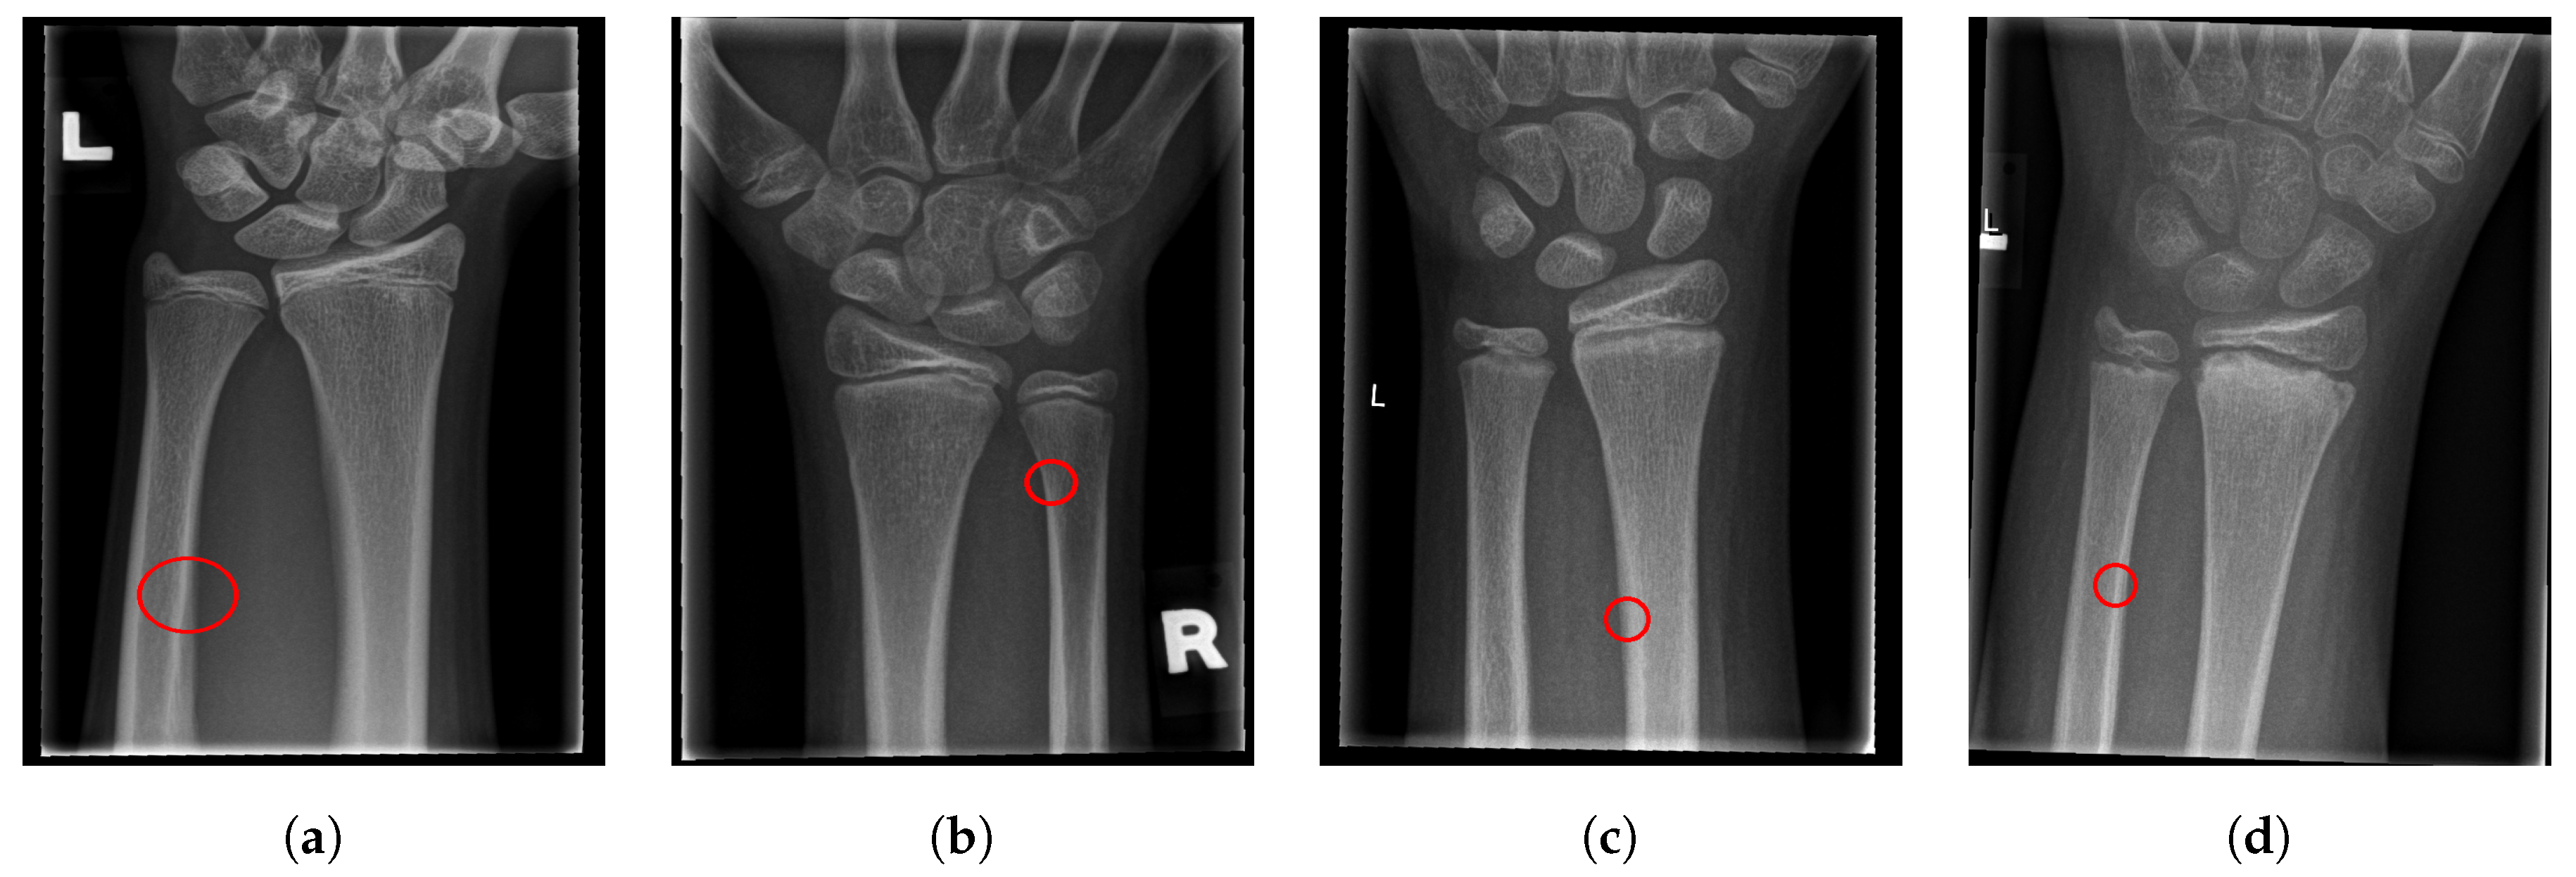

The final fracture detection and localisation results are shown in Figure 12, Figure 13, Figure 14 and Figure 15 (denoted by blue lines). Figure 12 and Figure 13 show two peaks which represent potential fractures. The critical fracture area is marked in the X-ray image by a red circle (at the centre of which is the coordinate of the highest peak, with radius being defined by the width of the area), as shown in Figure 16.

Figure 16.

Fracture area detection.

As can be seen, the proposed method was shown to be efficient, not only in detecting the fractures in the images (flagging the images as either containing fractures or fracture-free), but also precisely localising the position and the size of the region with the fracture. This can be used to assist medical staff to consider only the images with fractures and to direct their attention to specific regions of interests containing demanding fractures.

For illustration, four images from each class (TP, TN, FP, and FN) are given in Figure 17, Figure 18, Figure 19 and Figure 20.

Figure 17.

Examples from the true positive (TP) performance metric class.